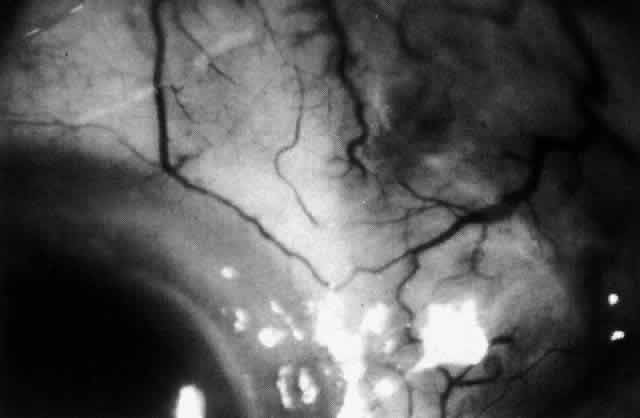

Because the posterior sclera is invisible, the diagnosis of posterior scleritis is made only if the anterior sclera is also involved or some other sign or symptom leads one to suspect it. Posterior scleritis is much more common than previously suspected, as recent clinical and pathologic studies have shown.19,28,29 There are two distinct forms of posterior scleritis. The first is usually associated with an anterior scleritis. This granulomatous disorder, like its anterior counterpart, can be diffuse, nodular, or necrotizing in character and is associated with the connective tissue diseases. The second form occurs in young patients of all races who are 9 to 40 years of age. It is always diffuse in character but is not associated with any systemic disorder. Both forms may cause uveitis if the inflammation affects the ciliary body, and in both forms the patient may develop exudative retinal detachments, choroidal folds, and swelling of the disc (Figs. 51 and 52). The granulomatous type may also involve the structures outside the globe, causing proptosis (Fig. 53), limitation of ocular muscle movement, and, uniquely, retraction of the lower lid on attempted elevation of the eye (Fig. 54). Diagnosis is with B-scan ultrasonography.

Fig. 51. Swelling of the optic nerve head and hemorrhage near the disc in a patient with posterior scleritis. The poor quality of the photograph is partly due to vitreous haze that accompanied the inflammation.

Fig. 52. Fundus appearance after resolution of exudative detachment in patient with severe posterior scleritis. Macula was affected and vision much impaired. (Watson PG: Management of scleritis. In: Recent Advances in Ophthalmology, Vol 5. London, Churchill-Livingstone, 1975)